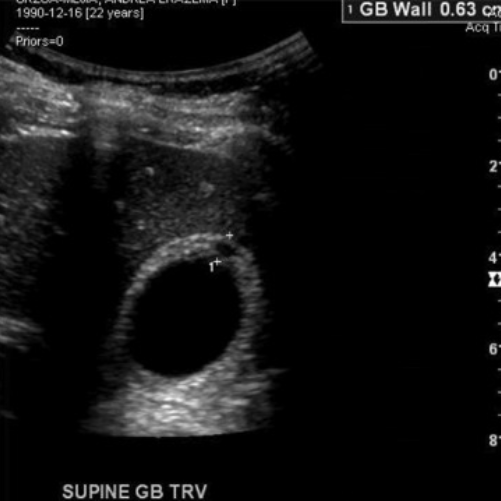

Thickend GB wall (>3 mm)

What is the normal gallbladder wall thickness and why is it important?

The wall should measure ≤3 mm; focal or diffuse thickening suggests pathology.